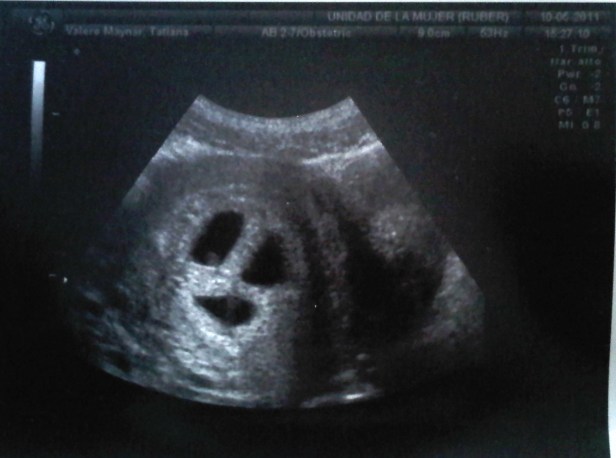

Muy a menudo me preguntan que sentí cuando me enteré que estaba embarazada de trillizos y como fueron los primeros años. Y siempre muestro esta foto porque fue el principio de todo…

Era la primera revisión después de saber que estaba embarazada y nada más pasarme el ecógrafo la ginecóloga se quedó callada. Yo le pregunté que pasaba y entonces me dijo: míralo tú misma. Me giró la pantalla y vi esta imagen. Sobraron las palabras.